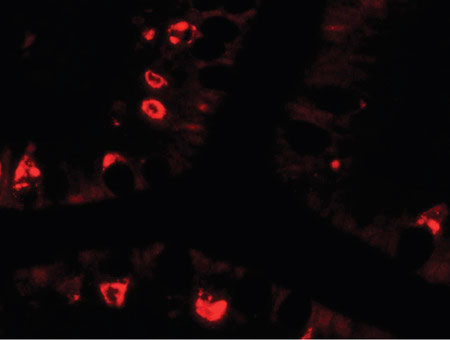

Immunofluorescence of AGR2 in human small intestine tissue with AGR2 antibody at 20 ug/ml.